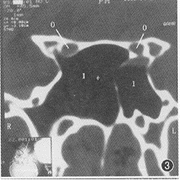

图1 正常视神经管轴位扫描图像,可见双侧视神经管与眶内段视神经同层显示,视神经管位居后内,呈前外走向后内的“轨道状”影像,与同侧眶内段视神经略向内成角,眶上裂位居其前外方,呈“裂隙状”,从眶尖指向正后方。双侧筛窦为半管型,左侧视神经管后半毗邻蝶窦,内侧壁1.1 mm,前半毗邻后筛,内侧壁0.4 mm,双侧蝶窦为Π°。

图3 冠状位扫描示正常视神经管在鞍结节稍前方层面呈对称的“蝶眼状”。

在轴位CT图像上,视神经管表现为较靠后内侧的“轨道状”影像,眶上裂在其前外侧方呈“裂隙状”,眶下裂在其前下方呈“狭谷状”影像(图1,2);在冠状位CT图像上,视神经管在鞍结节稍前方呈“蝶眼状”影像(图3),而眶上、下裂在其前方球后层面上,分别呈近水平位和垂直位“裂隙状”影像。

视神经管的解剖结构比较复杂,以前曾有尸头解剖结构的报道。视神经管在CT轴位和冠状位上能全方位的观察,在CT轴位图像上表现为对称的由前外斜向后内的“轨道状”影像,其内外轨为高密度的骨质影,而轨间则为相对低密度的软组织影(图1);冠状位图像上在鞍结节稍前方层面表现为蝶窦侧顶壁与蝶骨小翼围成的对称的“蝶眼状”影像,向前层面“蝶眼”逐渐向外下方分离(图3)。轴位图像上,眶上裂在视神经管前外侧,呈一“裂隙状”,在眶尖部朝向正后方(图1);眶下裂位于视神经管前下方,表现为由前外斜向后内的“狭谷状”影像(图2)。在冠状位图像上,于视神经管前方层面上,眶上裂、眶下裂可同时显示于眶内段视神经的外上方和下方,前者近乎水平位并略向外上倾斜,后者近乎垂直位略向外下倾斜,两者夹角近90°。